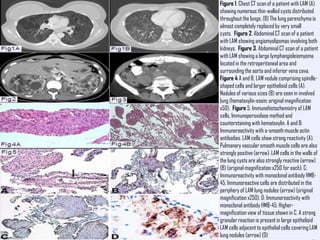

Figure 1. Chest CT scan of a patient with LAM (A)

showing numerous thin-walled cysts distributed

throughout the lungs. (B) The lung parenchyma is

almost completely replaced by very small

cysts. Figure 2. Abdominal CT scan of a patient

*CT scan and high-resolution CT scan findings include

the following:

 Diffuse thin-walled cysts - The defining appearance in LAM